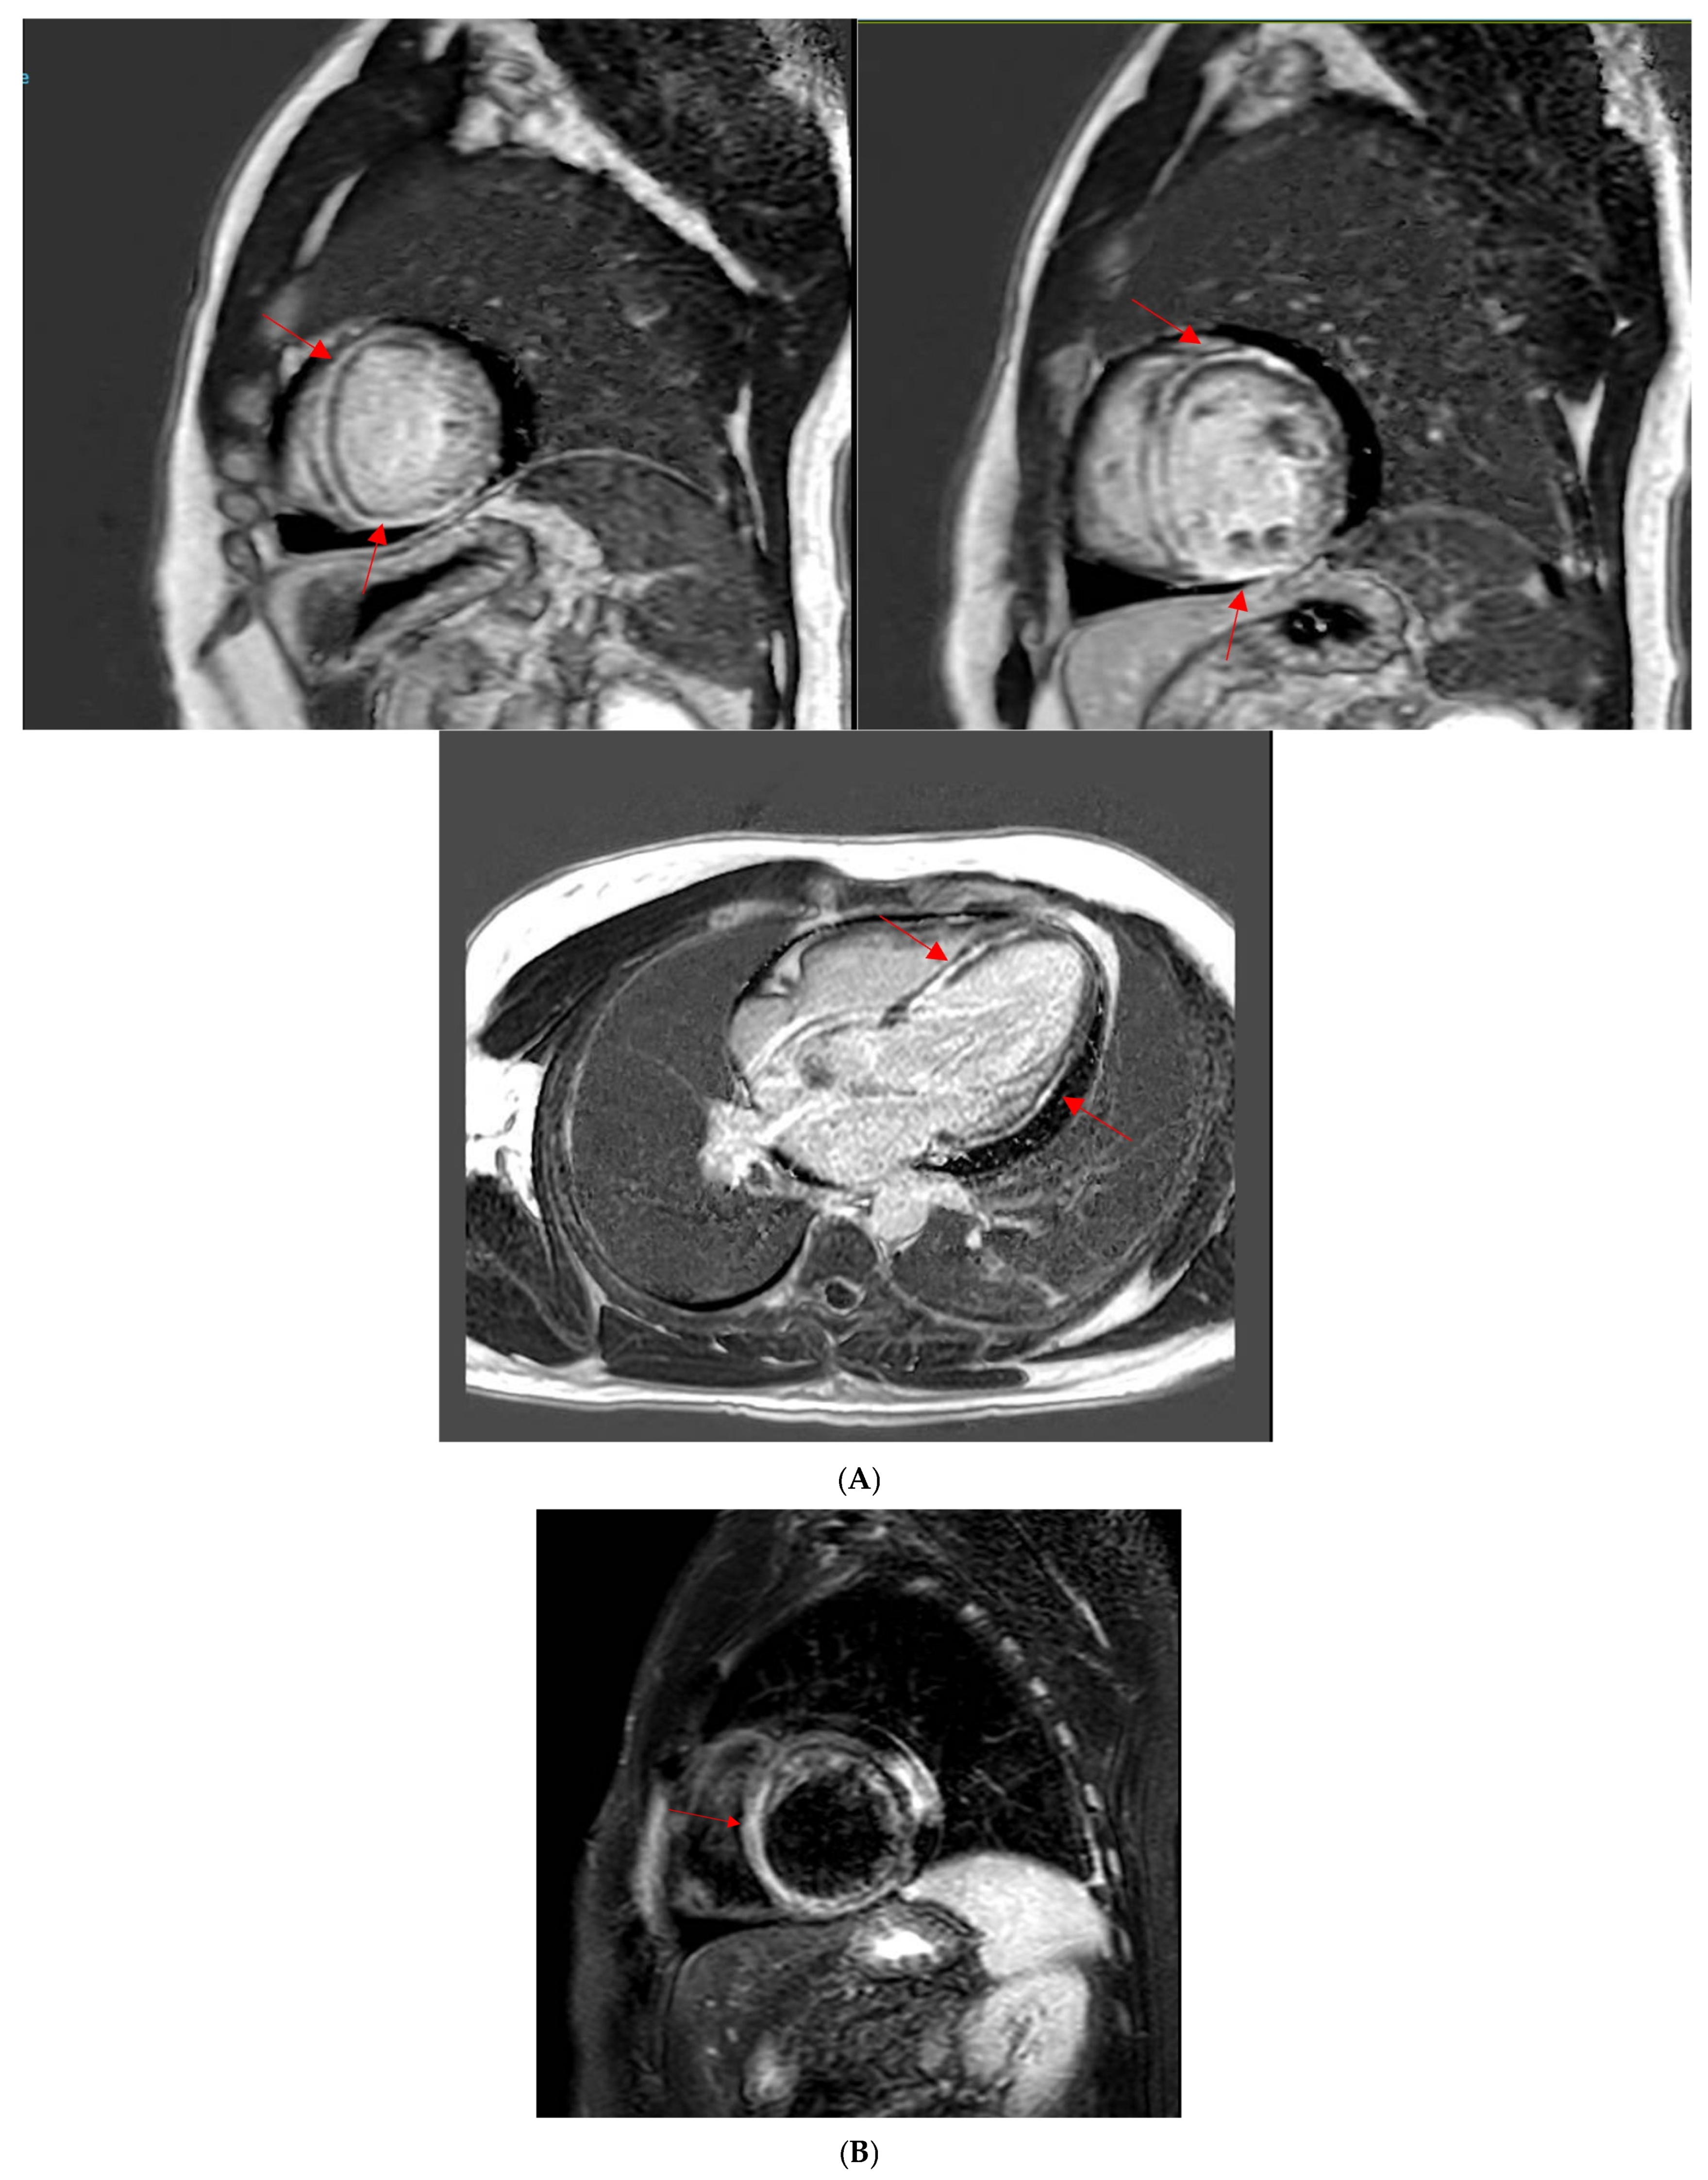

2.2. Cardiac Magnetic Resonance Imaging

- Ferreira, V.M.; Schulz-Menger, J.; Holmvang, G.; Kramer, C.M.; Carbone, I.; Sechtem, U.; Kindermann, I.; Gutberlet, M.; Cooper, L.T.; Liu, P.; et al. Cardiovascular Magnetic Resonance in Nonischemic Myocardial Inflammation: Expert Recommendations. J. Am. Coll. Cardiol. 2018, 72, 3158–3176. [Google Scholar] [CrossRef]

- Zhang, L.; Awadalla, M.; Mahmood, S.S.; Nohria, A.; Hassan, M.Z.O.; Thuny, F.; Zlotoff, D.A.; Murphy, S.P.; Stone, J.R.; Golden, D.L.A.; et al. Cardiovascular magnetic resonance in immune checkpoint inhibitor-associated myocarditis. Eur. Heart J. 2020, 41, 1733–1743. [Google Scholar] [CrossRef] [PubMed]

- Aquaro, G.D.; Perfetti, M.; Camastra, G.; Monti, L.; Dellegrottaglie, S.; Moro, C.; Pepe, A.; Todiere, G.; Lanzillo, C.; Scatteia, A.; et al. Cardiac MR With Late Gadolinium Enhancement in Acute Myocarditis With Preserved Systolic Function: ITAMY Study. J. Am. Coll. Cardiol. 2017, 70, 1977–1987. [Google Scholar] [CrossRef] [PubMed]

- Mahrholdt, H.; Wagner, A.; Deluigi, C.C.; Kispert, E.; Hager, S.; Meinhardt, G.; Vogelsberg, H.; Fritz, P.; Dippon, J.; Bock, C.T.; et al. Presentation, patterns of myocardial damage, and clinical course of viral myocarditis. Circulation 2006, 114, 1581–1590. [Google Scholar] [CrossRef] [PubMed]

- Cadour, F.; Cautela, J.; Rapacchi, S.; Varoquaux, A.; Habert, P.; Arnaud, F.; Jacquier, A.; Meilhac, A.; Paganelli, F.; Lalevée, N.; et al. Cardiac MRI Features and Prognostic Value in Immune Checkpoint Inhibitor-induced Myocarditis. Radiology 2022, 303, 512–521. [Google Scholar] [CrossRef]

- Thavendiranathan, P.; Zhang, L.; Zafar, A.; Drobni, Z.D.; Mahmood, S.S.; Cabral, M.; Awadalla, M.; Nohria, A.; Zlotoff, D.A.; Thuny, F.; et al. Myocardial T1 and T2 Mapping by Magnetic Resonance in Patients With Immune Checkpoint Inhibitor-Associated Myocarditis. J. Am. Coll. Cardiol. 2021, 77, 1503–1516. [Google Scholar] [CrossRef]

- Zhao, S.H.; Yun, H.; Chen, C.Z.; Chen, Y.Y.; Lin, J.Y.; Zeng, M.S.; Liu, T.S.; Pan, C.Z.; Jin, H. The prognostic value of global myocardium strain by CMR-feature tracking in immune checkpoint inhibitor-associated myocarditis. Eur. Radiol. 2022, 32, 7657–7667. [Google Scholar] [CrossRef]

- Wintersperger, B.J.; Calvillo-Argüelles, O.; Lheureux, S.; Houbois, C.P.; Spreafico, A.; Bedard, P.L.; Neilan, T.G.; Thavendiranathan, P. Immune checkpoint inhibitor-related myocarditis: An illustrative case series of applying the updated Cardiovascular Magnetic Resonance Lake Louise Criteria. Eur. Heart J. Case Rep. 2022, 6, ytab478. [Google Scholar] [CrossRef]

- Faron, A.; Isaak, A.; Mesropyan, N.; Reinert, M.; Schwab, K.; Sirokay, J.; Sprinkart, A.M.; Bauernfeind, F.G.; Dabir, D.; Pieper, C.C.; et al. Cardiac MRI Depicts Immune Checkpoint Inhibitor-induced Myocarditis: A Prospective Study. Radiology 2021, 301, 602–609. [Google Scholar] [CrossRef]